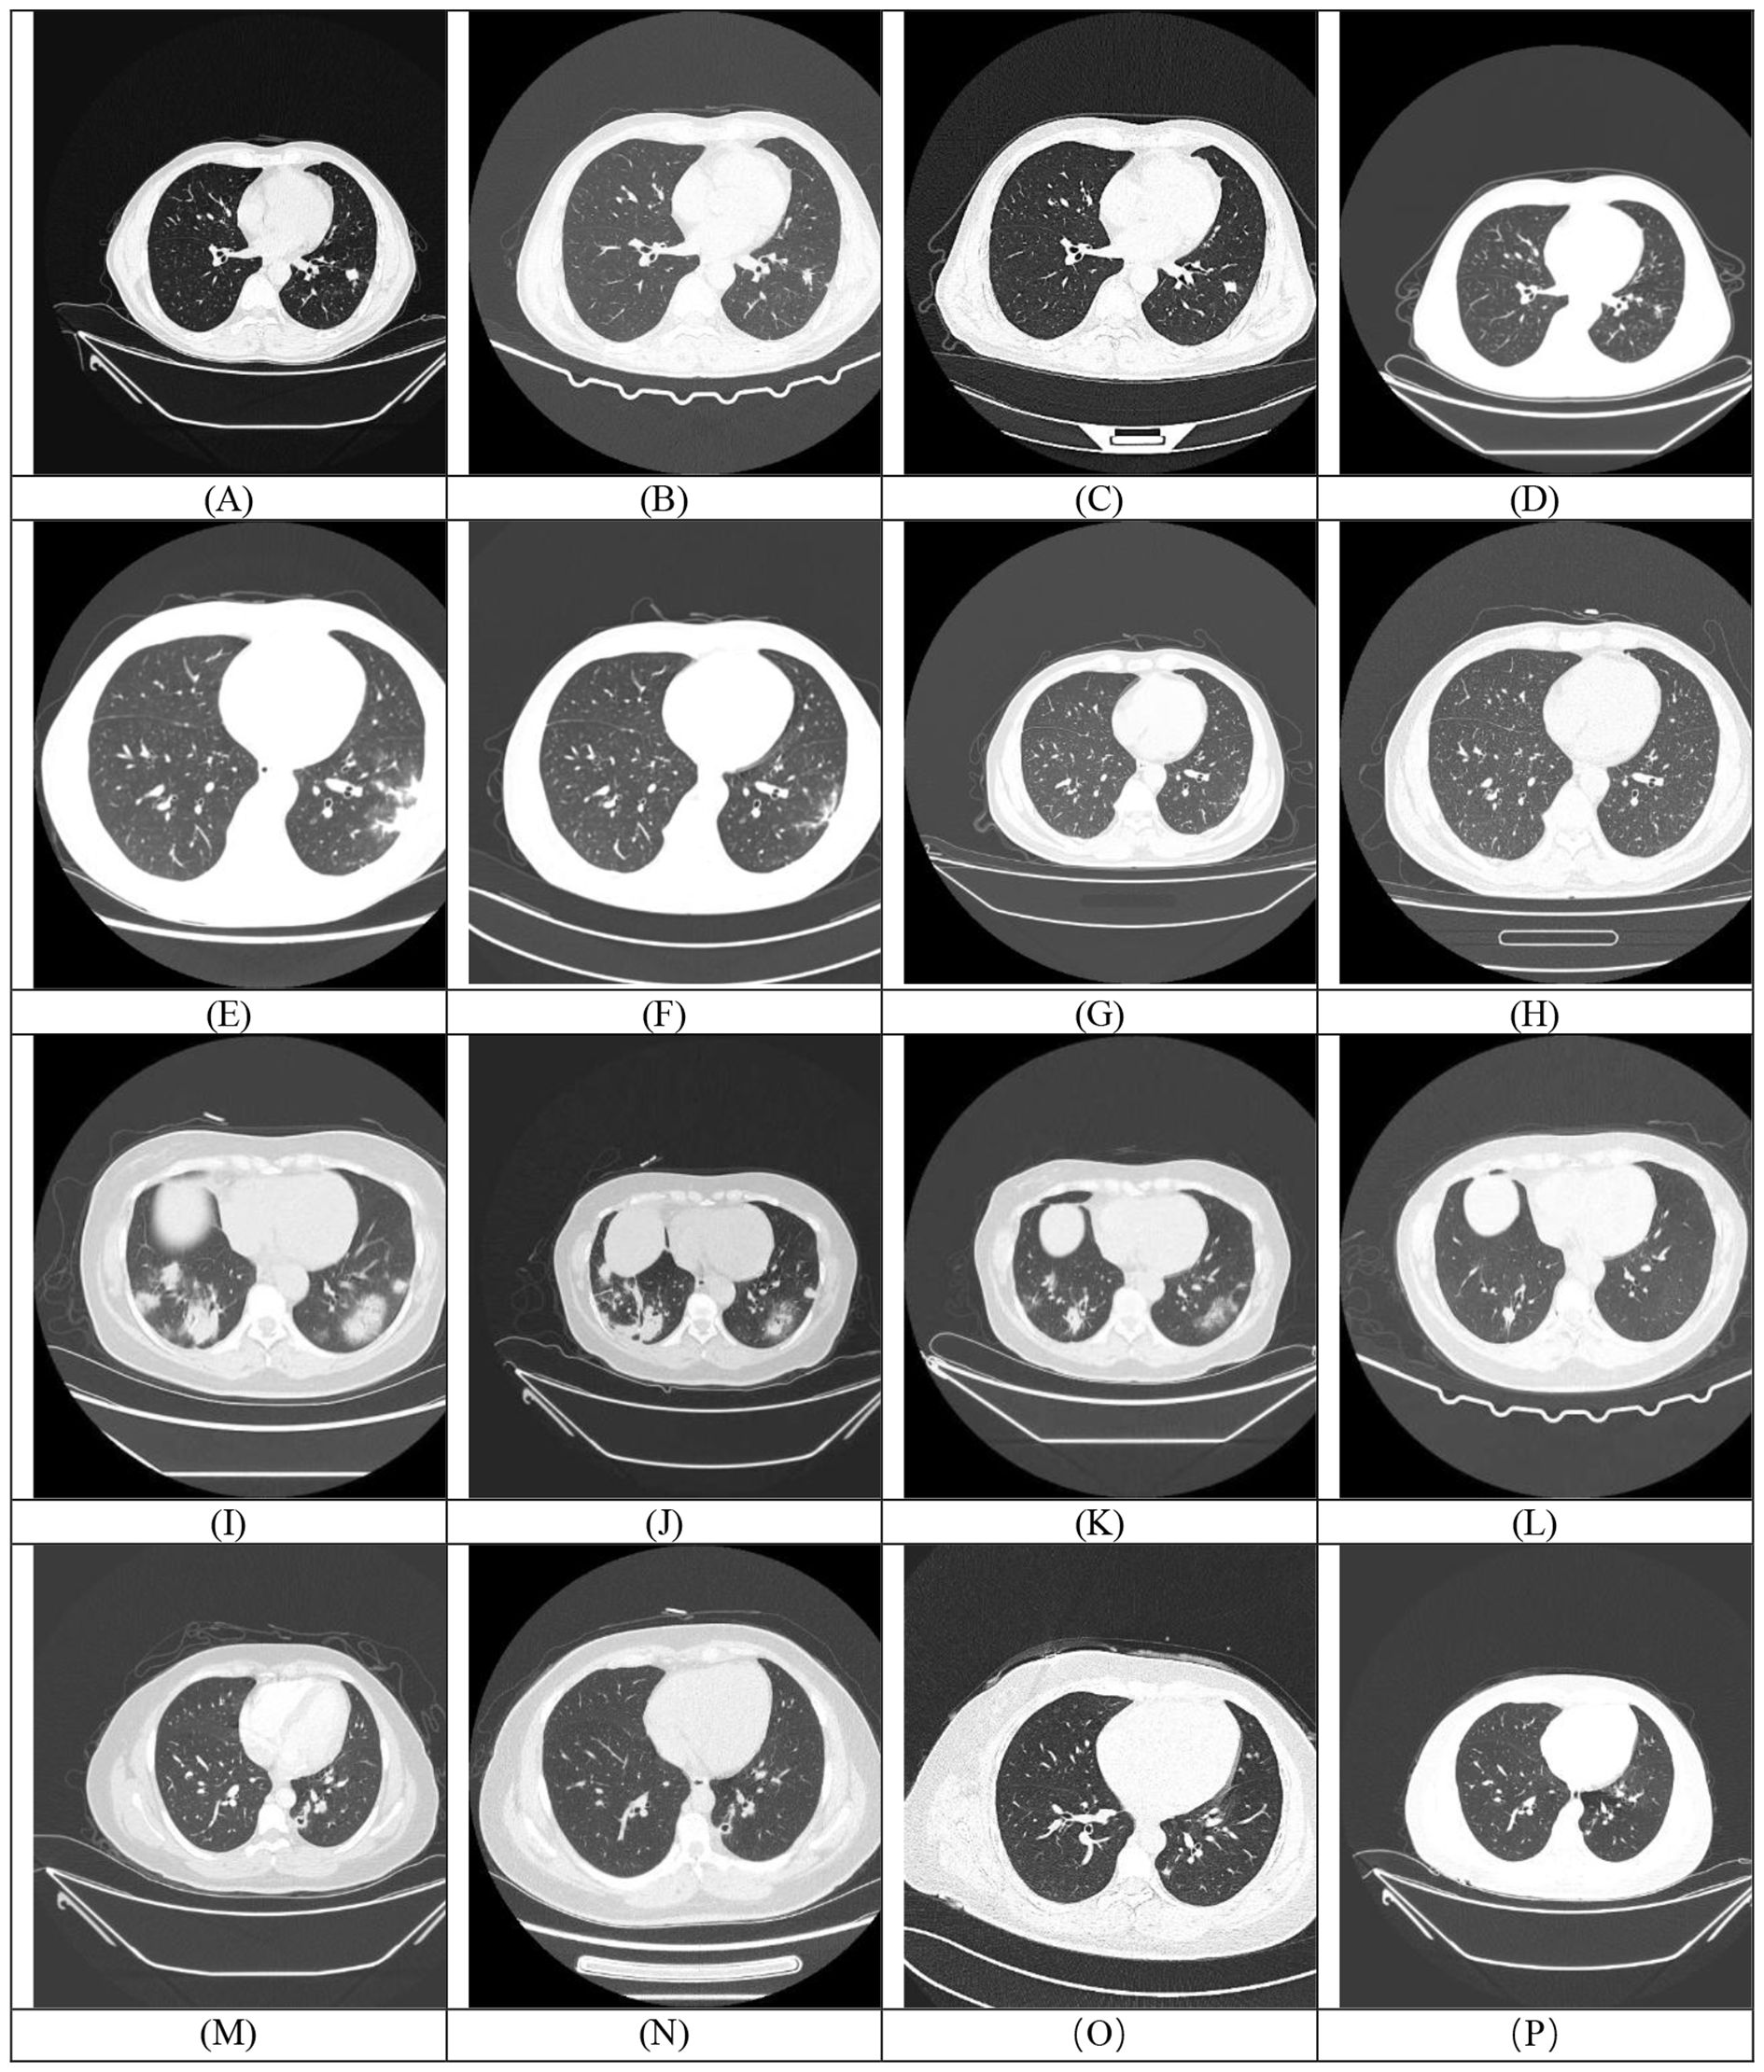

Among the 31 enrolled patients, 4 (12.50%) died during hospitalization. Of the 27 survivors, follow-up revealed 1 case (3.70%) of disease recurrence, one death (3.70%) from brain metastasis secondary to a lung tumor, and 1 patient (3.70%) lost to follow-up. Most patients undergoing repeat chest CT scans within one to three months of initial evaluation. Among the patients with follow-up CT imaging data (n=14), the comparison of CT manifestations before and after treatment in some cases is shown in Figure 4. Among these 14 patients, 3 cases (21.43%) achieved complete lesion resolution, 7 (50.00%) exhibited sustained improvement with reduced lesion size, 3 (21.43%) showed partial radiographic improvement, and only 1 patient (7.14%, 1/14) experienced disease progression.

Figure 4. Each row (Rows 1-4) corresponds to a single patient. The first image in each row (A, E, I, M) represents the baseline (pre-treatment) scan, while the subsequent images (B-D, F-H, J-L, N-P) are post-treatment follow-up scans demonstrating temporal changes in the lesions.